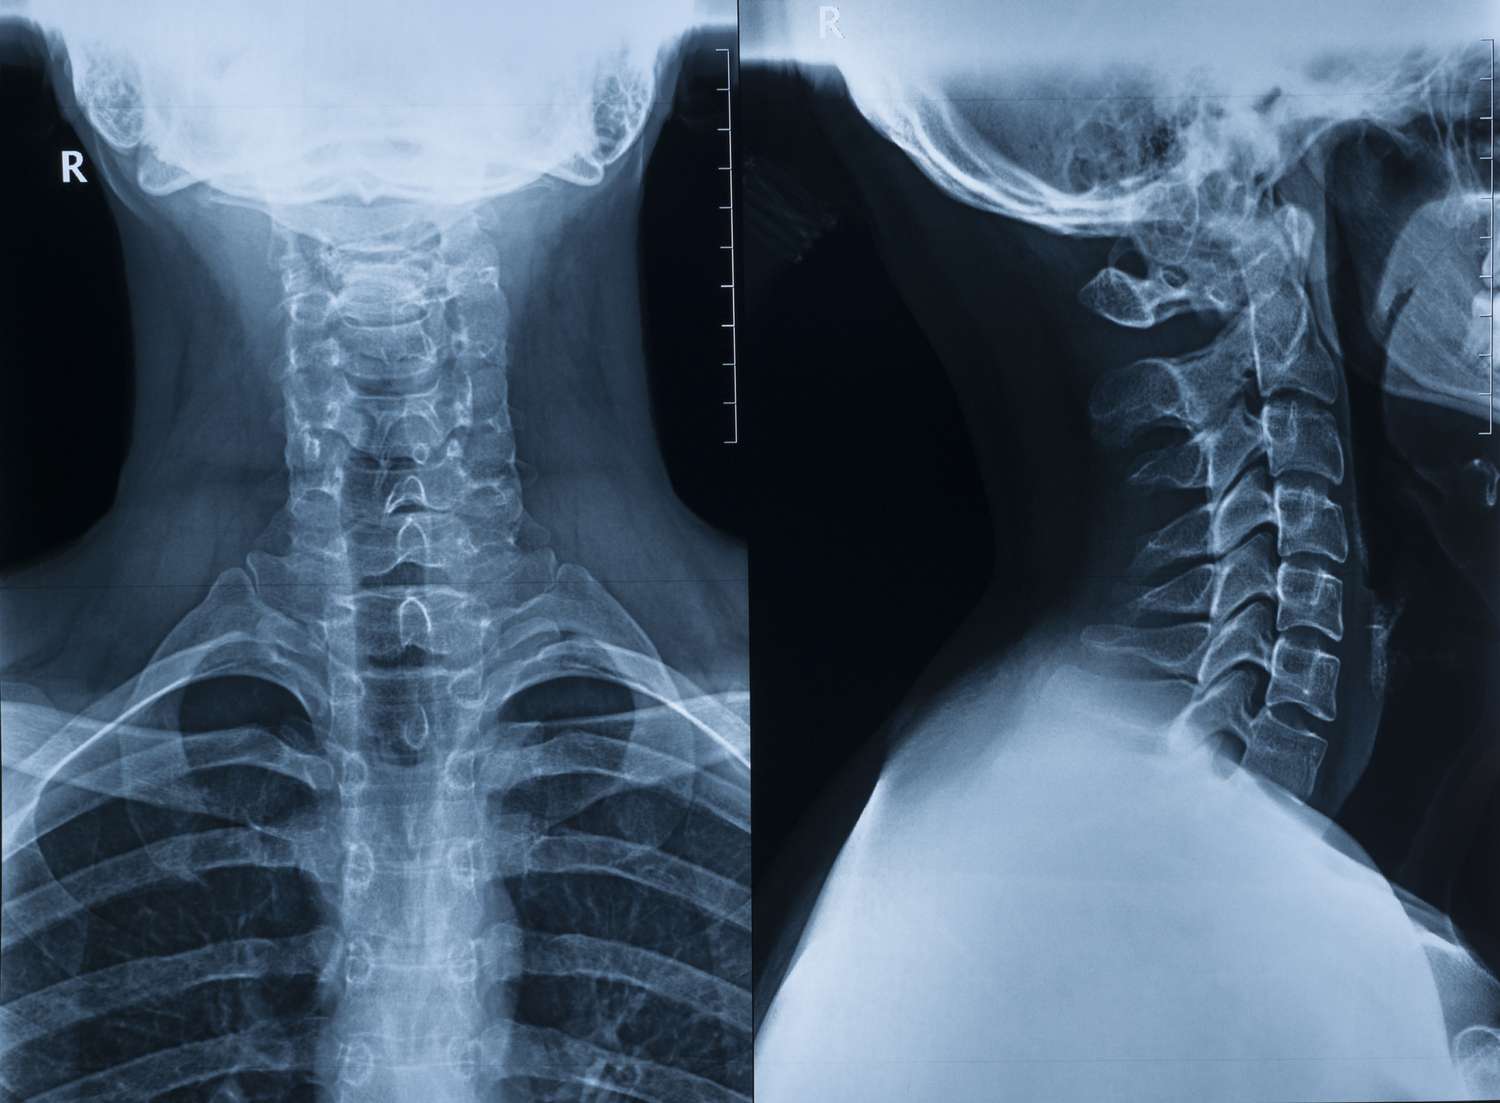

Understanding Cervical Rib & Thoracic Outlet Syndrome

Cervical Rib and Thoracic Outlet Syndrome (TOS) are conditions caused by compression of blood vessels or nerves between the collarbone and the first rib. This compression leads to pain, numbness, tingling, and weakness in the arms or shoulders.

A cervical rib is an extra rib that sometimes develops above the first rib and can contribute to thoracic outlet compression.

Diagnosis at Prime Vascular Care

Dr. Vishal Sheth conducts a thorough physical examination and uses advanced imaging to pinpoint the exact cause of compression.

Diagnostic tools include:-

Doppler Ultrasound to assess blood flow

CT or MRI Angiography for detailed vascular imaging

Nerve conduction studies (if neurological symptoms are present